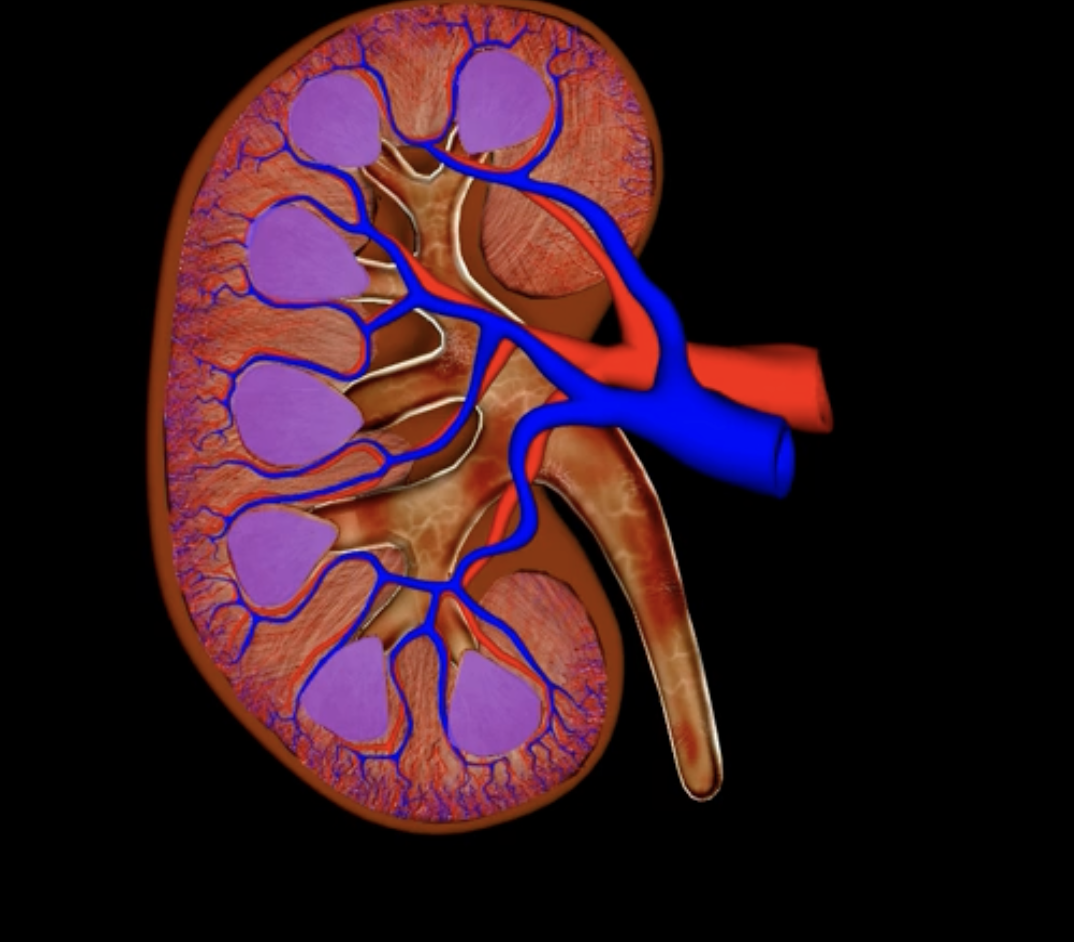

renal pyramids

purple

renal papilla

green

minor calyx

teal

major calyces

blue

renal pelvis

minor and major calyces

renal medulla

renal lobe